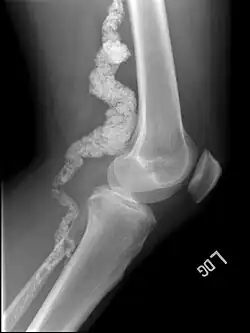

A knee x-ray of a person with ACDC | |

Arterial calcification due to deficiency of CD73 (ACDC) is a rare genetic disorder that causes calcium buildup in the arteries and joints of the hands and feet, and other areas below the waist.[1] Although patients exhibiting these symptoms have been identified as early as 1914, this disorder had not been studied extensively until recently. The identification of the specific ACDC gene and mutations occurred in 2011. ACDC is caused by a mutation in the NT5E gene, which prevents calcium-removing agents from functioning.[1][2] Patients with this mutation experience chronic pain, difficulty moving, and an increased risk of cardiovascular problems.[1][2] In experiments at the molecular level, treatment with adenosine or a phosphatase inhibitor reversed and prevented calcification, suggesting they could be used as possible treatment methods.[1] There is currently no cure for ACDC, and patients have limited treatment options, which focus primarily on the removal of blood calcium and improving mobility.[1][2]